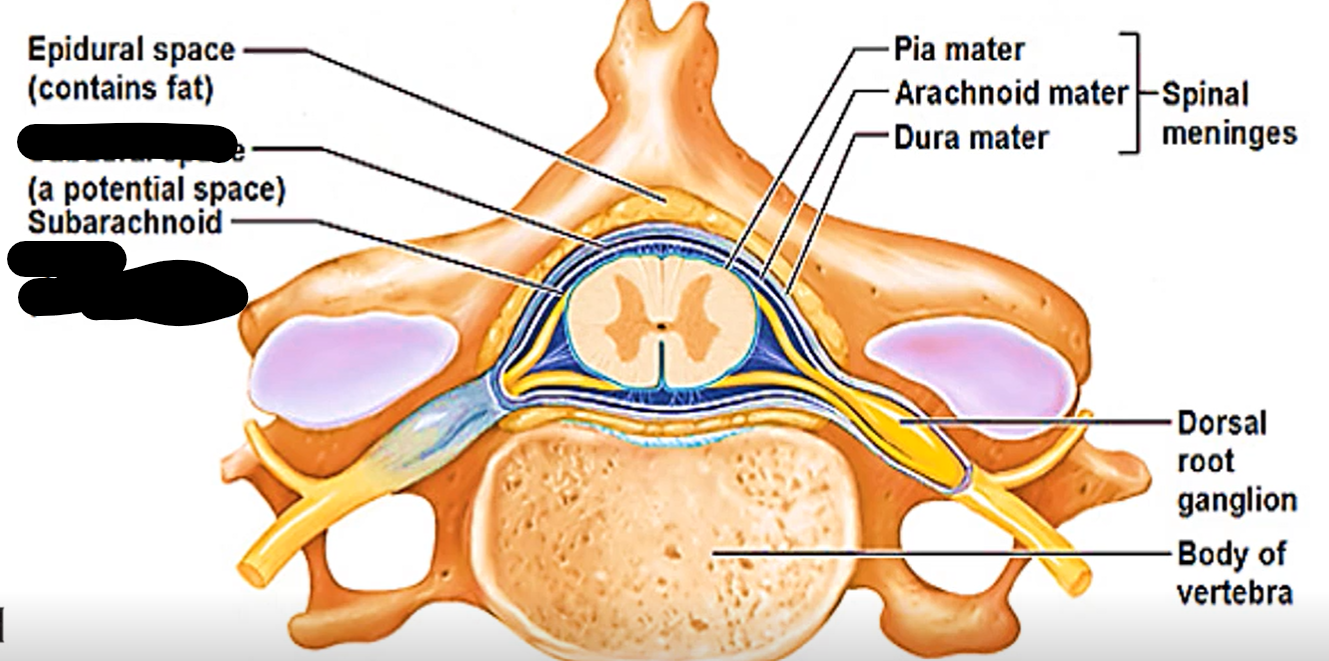

How many layers of meninges

3

Layer of meninges from superficial to deep

Dura mater

Arachnoid mater

Pia mater

What are the two layers of dura mater?

Periosteal dura mater

Meningeal dura mater

Where is epidural and subdural space?

In spinal cord (contains fat) or brain (potential space)

What does epidural space separate in spinal cord?

Between vertebrae and dura mater

Epidural space (contains fat)

Subdural space (contains CSF)

What does subdural space separate?

Dura mater and arachnoid mater

What does subarachnoid space separate?

Arachnoid mater and pia mater